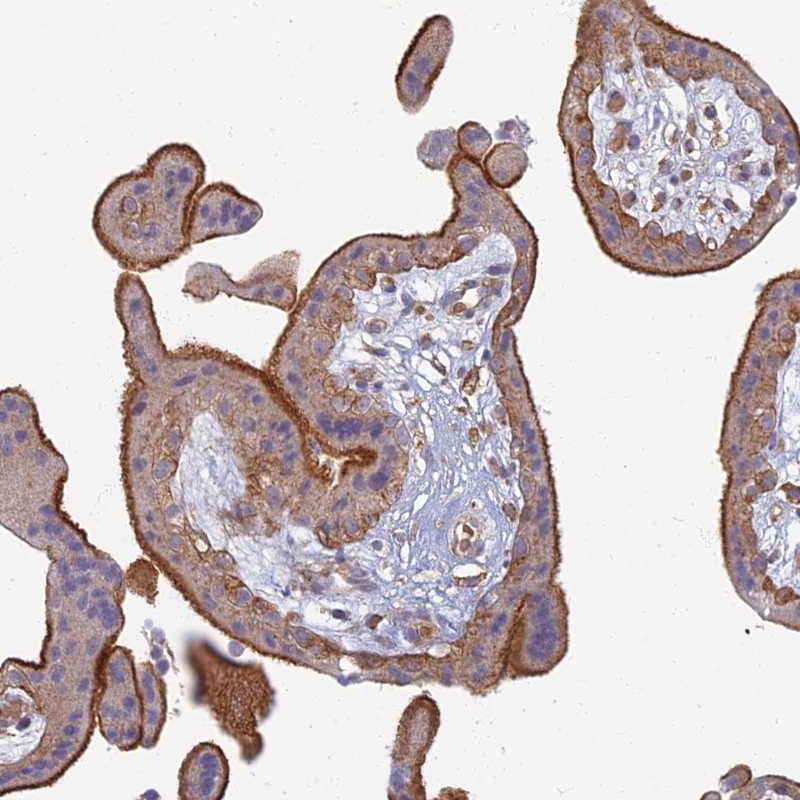

Immunohistochemical staining of human placenta shows strong membranous and cytoplasmic positivity in trophoblastic cells.